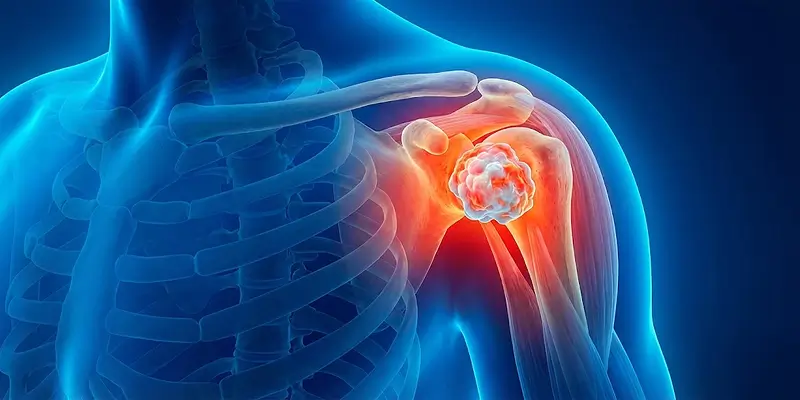

Kemik tümörleri, ortopedi ve travmatoloji alanında uzman görüşleri, güncel tedavi yöntemleri ve hasta hikayeleri ile bilgilendirici içerikler.

Kemik tümörü (kanseri) nedir, kaç çeşittir? İyi huylu ve kötü huylu kemik lezyonlarına genel bakış ve Dr. Arıkan'ın tedavi yaklaşımı.

Dev hücreli kemik tümörü, osteoklastik dev hücrelerin kontrolsüz çoğalmasıyla oluşan agresif bir kemik tümörüdür. Belirtileri, tanı yöntemleri ve tedavi seçenekleri.

Gece artan kemik ağrısı, geçmeyen şişlikler ve sebepsiz kırıklar kemik tümörü habercisi olabilir. Erken tanı hayat kurtarır, belirtileri öğrenin.